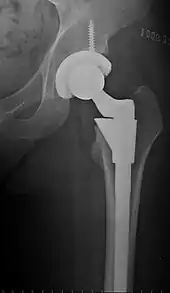

Post-operative projectional radiography is routinely performed to ensure proper configuration of hip prostheses.

The direction of the acetabular cup influences the range of motion of the leg, and also affects the risk of dislocation.[9] For this purpose, the acetabular inclination and the acetabular anteversion are measurements of cup angulation in the coronal plane and the sagittal plane, respectively.

Acetabular anteversion.[81] This parameter is calculated on a lateral radiograph as the angle between the transverse plane and a line going through the (anterior and posterior) margins of the acetabular cup.[81]

Acetabular anteversion is normally between 5 and 25°.[9] An anteversion below or above this range increases the risk of dislocation.[9] There is an intra-individual variability in this method because the pelvis may be tilted in various degrees in relation to the transverse plane.[9]

Center of rotation: The horizontal center of rotation is calculated as the distance between the acetabular teardrop and the center of the head (or caput) of the prosthesis and/or the native femoral head on the contralateral side.[80] The vertical center of rotation instead uses the transischial line for reference.[80] The parameter should be equal on both sides.[80]